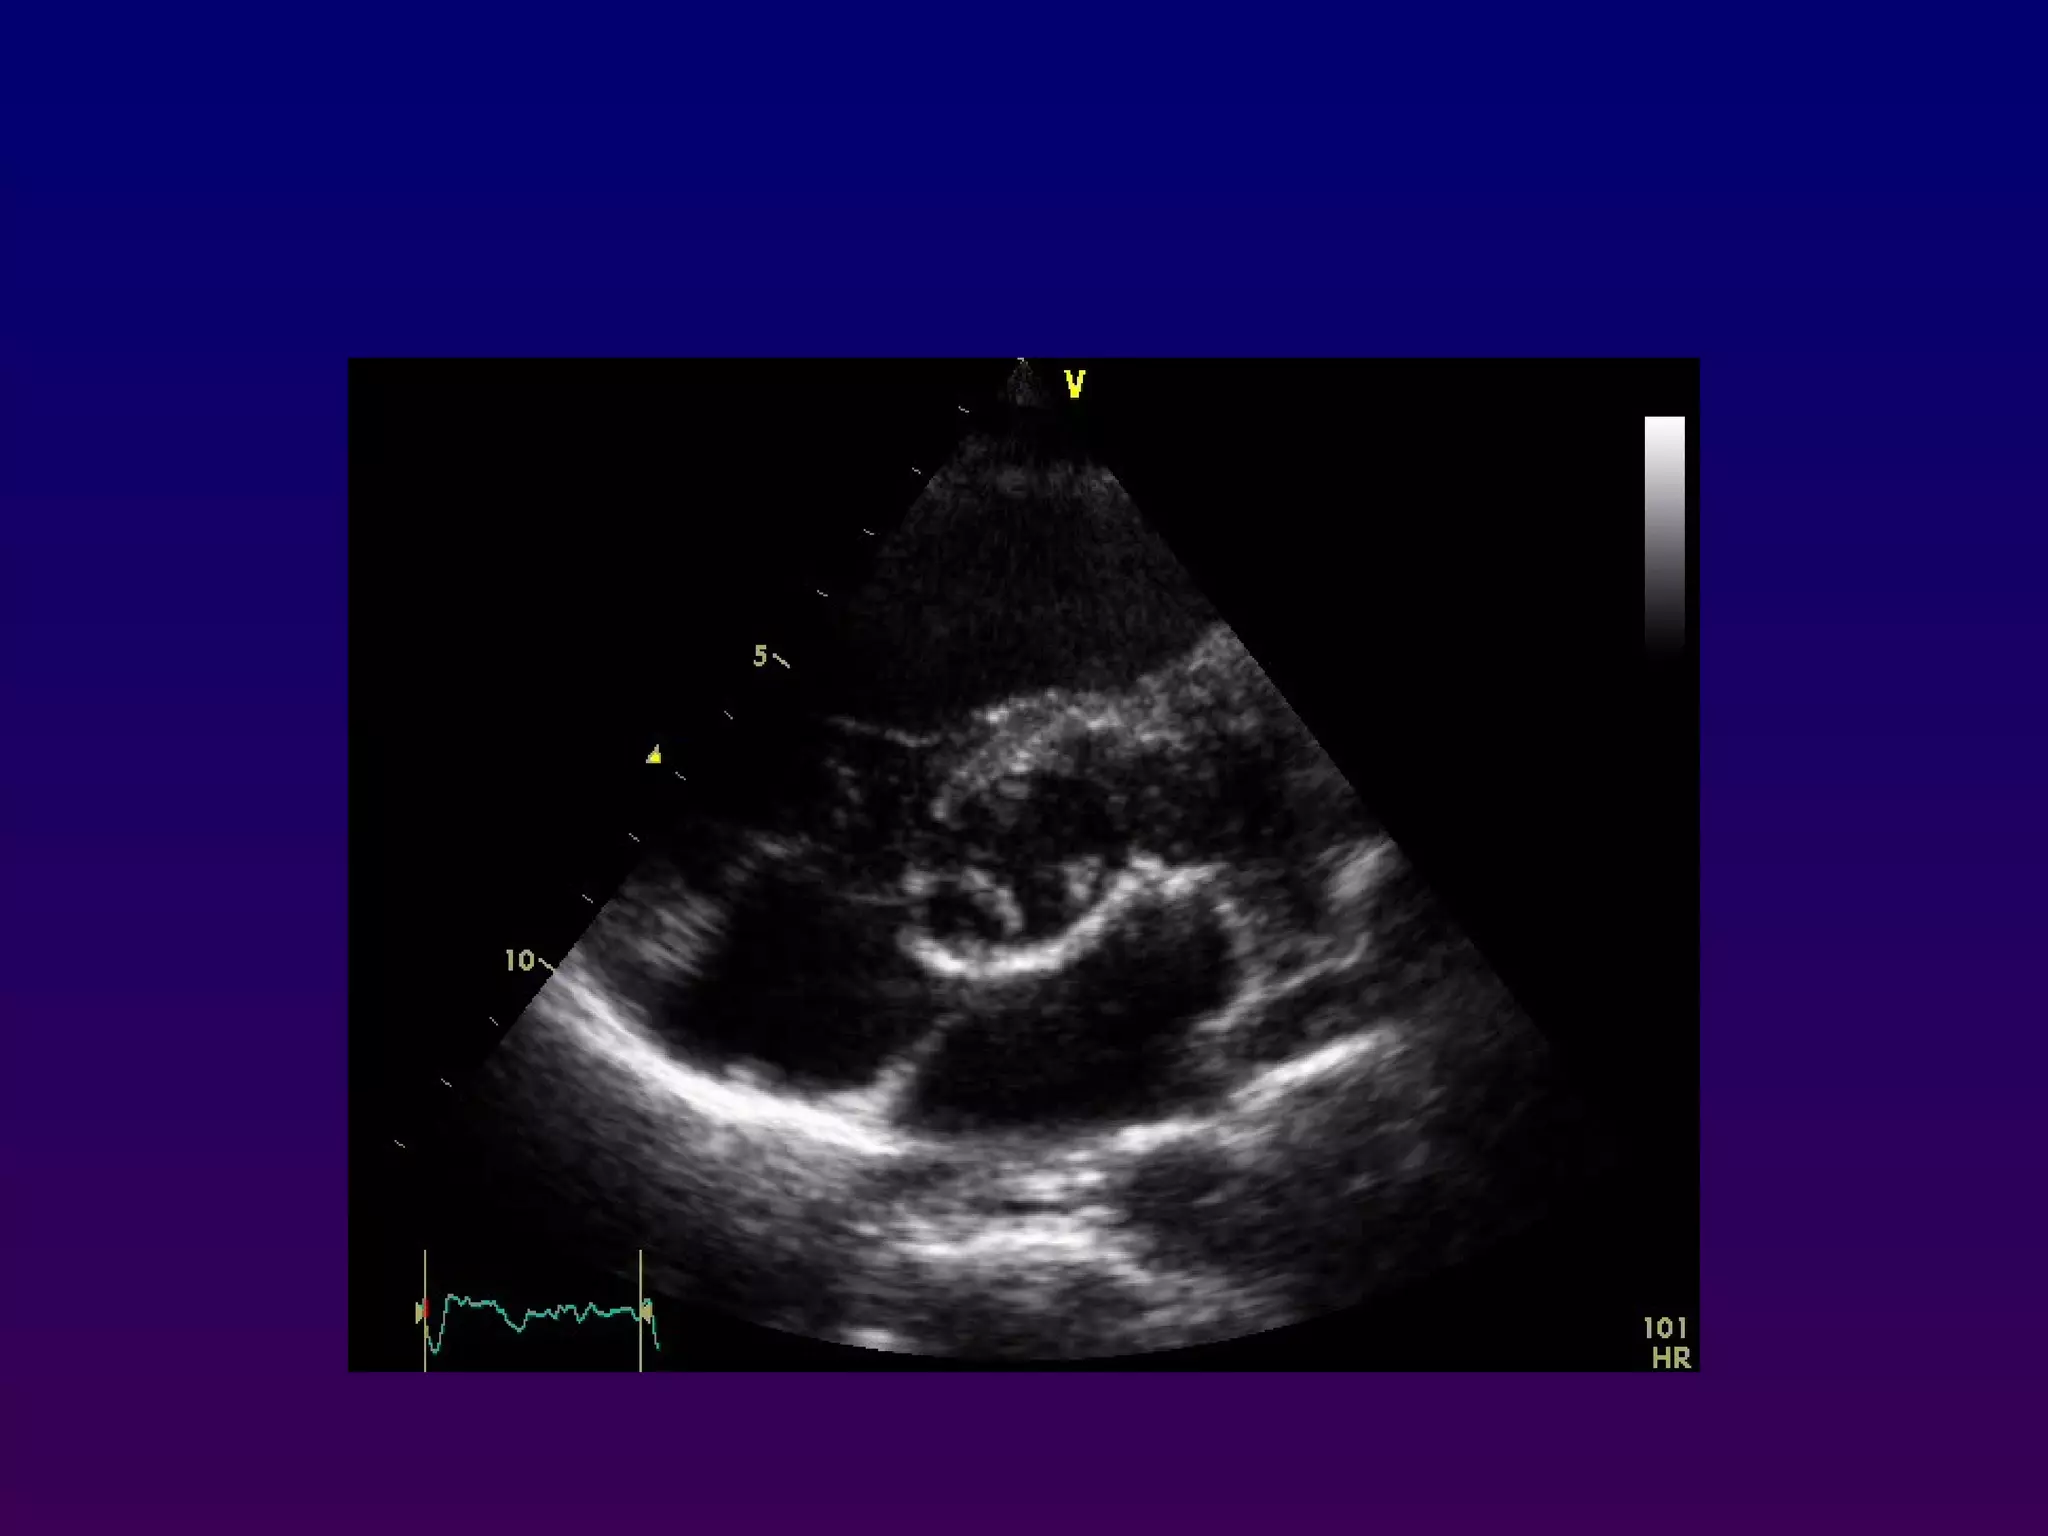

With the patient maintained in the left lateral

decubitus position, the transducer is placed near

the apex of the heart with an inferior orientation

In the apical four-chamber view, all four

chambers of the heart may be seen The left

ventricle appears as a truncated ellipse,RV

triangular with the interventricular septum, apex

formed by LV, and lateral walls visualized.

Apical four-chamber